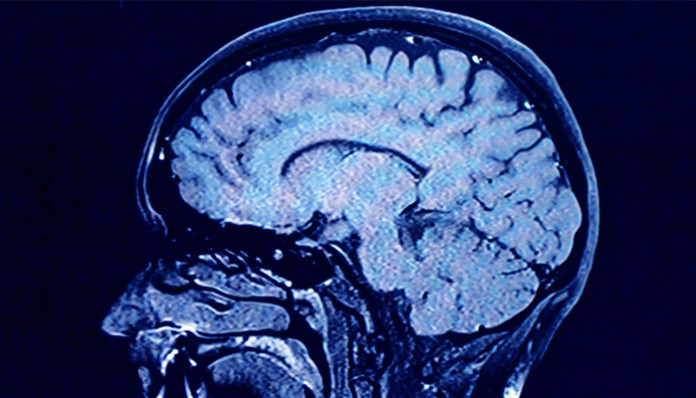

La función del cerebro de las personas adictas a la cocaína es diferente de la de las personas que no son adictos y, a menudo tienen un comportamiento altamente impulsivo, según un nuevo estudio científico.

La variación en la forma en que las diferentes regiones del cerebro se conectan, se comunican y función en las personas adictas a la cocaína es una observación al descubierto por primera vez por un equipo de investigación en colaboración liderado por la Universidad de Texas Medical Branch en Galveston y Virginia Commonwealth University. Estos hallazgos fueron publicados recientemente en NeuroImage: Clínica.

Los investigadores estudian tradicionalmente diferencias en la actividad cerebral regional utilizando imágenes de resonancia magnética funcional. Los investigadores en este estudio tomaron análisis de fMRI un paso más para descifrar las conexiones y dirección del flujo de información entre las regiones del cerebro, tanto en la cocaína y los usuarios no cocaína, utilizando una técnica basada en la resonancia magnética funcional llamado Dinámica Causal Modelado. La proyección de imagen basada en DCM proporciona una nueva herramienta para estudiar la conectividad cerebral y estrategias del diseño y desarrollo de medicamentos que pueden aumentar y / o restaurar dicho deterioro en el trastorno por consumo de cocaína.

En el estudio participaron 13 consumidores de cocaína y 10 usuarios que no son de cocaína para evaluar la conectividad cerebral durante la realización de la tarea Go / No Pasa dentro de un escáner de resonancia magnética funcional. Tanto los consumidores de cocaína y de los usuarios de cocaína no realizan la tarea igual de bien, lo que sugiere que la capacidad promedio para inhibir una respuesta fue la misma en los dos grupos. Sin embargo, hubo diferencias intrigantes entre los consumidores de cocaína y no usuarios en la fuerza de la comunicación entre las estructuras cerebrales clave.

El caudado izquierdo, una estructura cerebral conocida para controlar la función motora, se vio activada en ambos grupos de sujetos durante la inhibición de respuesta No Pasa. Sin embargo, las estructuras corticales del cerebro que regulan la actividad caudado izquierdo difirieron entre los consumidores de cocaína y los usuarios no cocaína durante preguntas más difíciles de la tarea Go / No Pasa.

drogas funcionales, cerebro y comunicación, Imágenes de Resonancia Magnética Funcional en Adictos a la Cocaína, resonancia magnética cerebral de un cocainomano